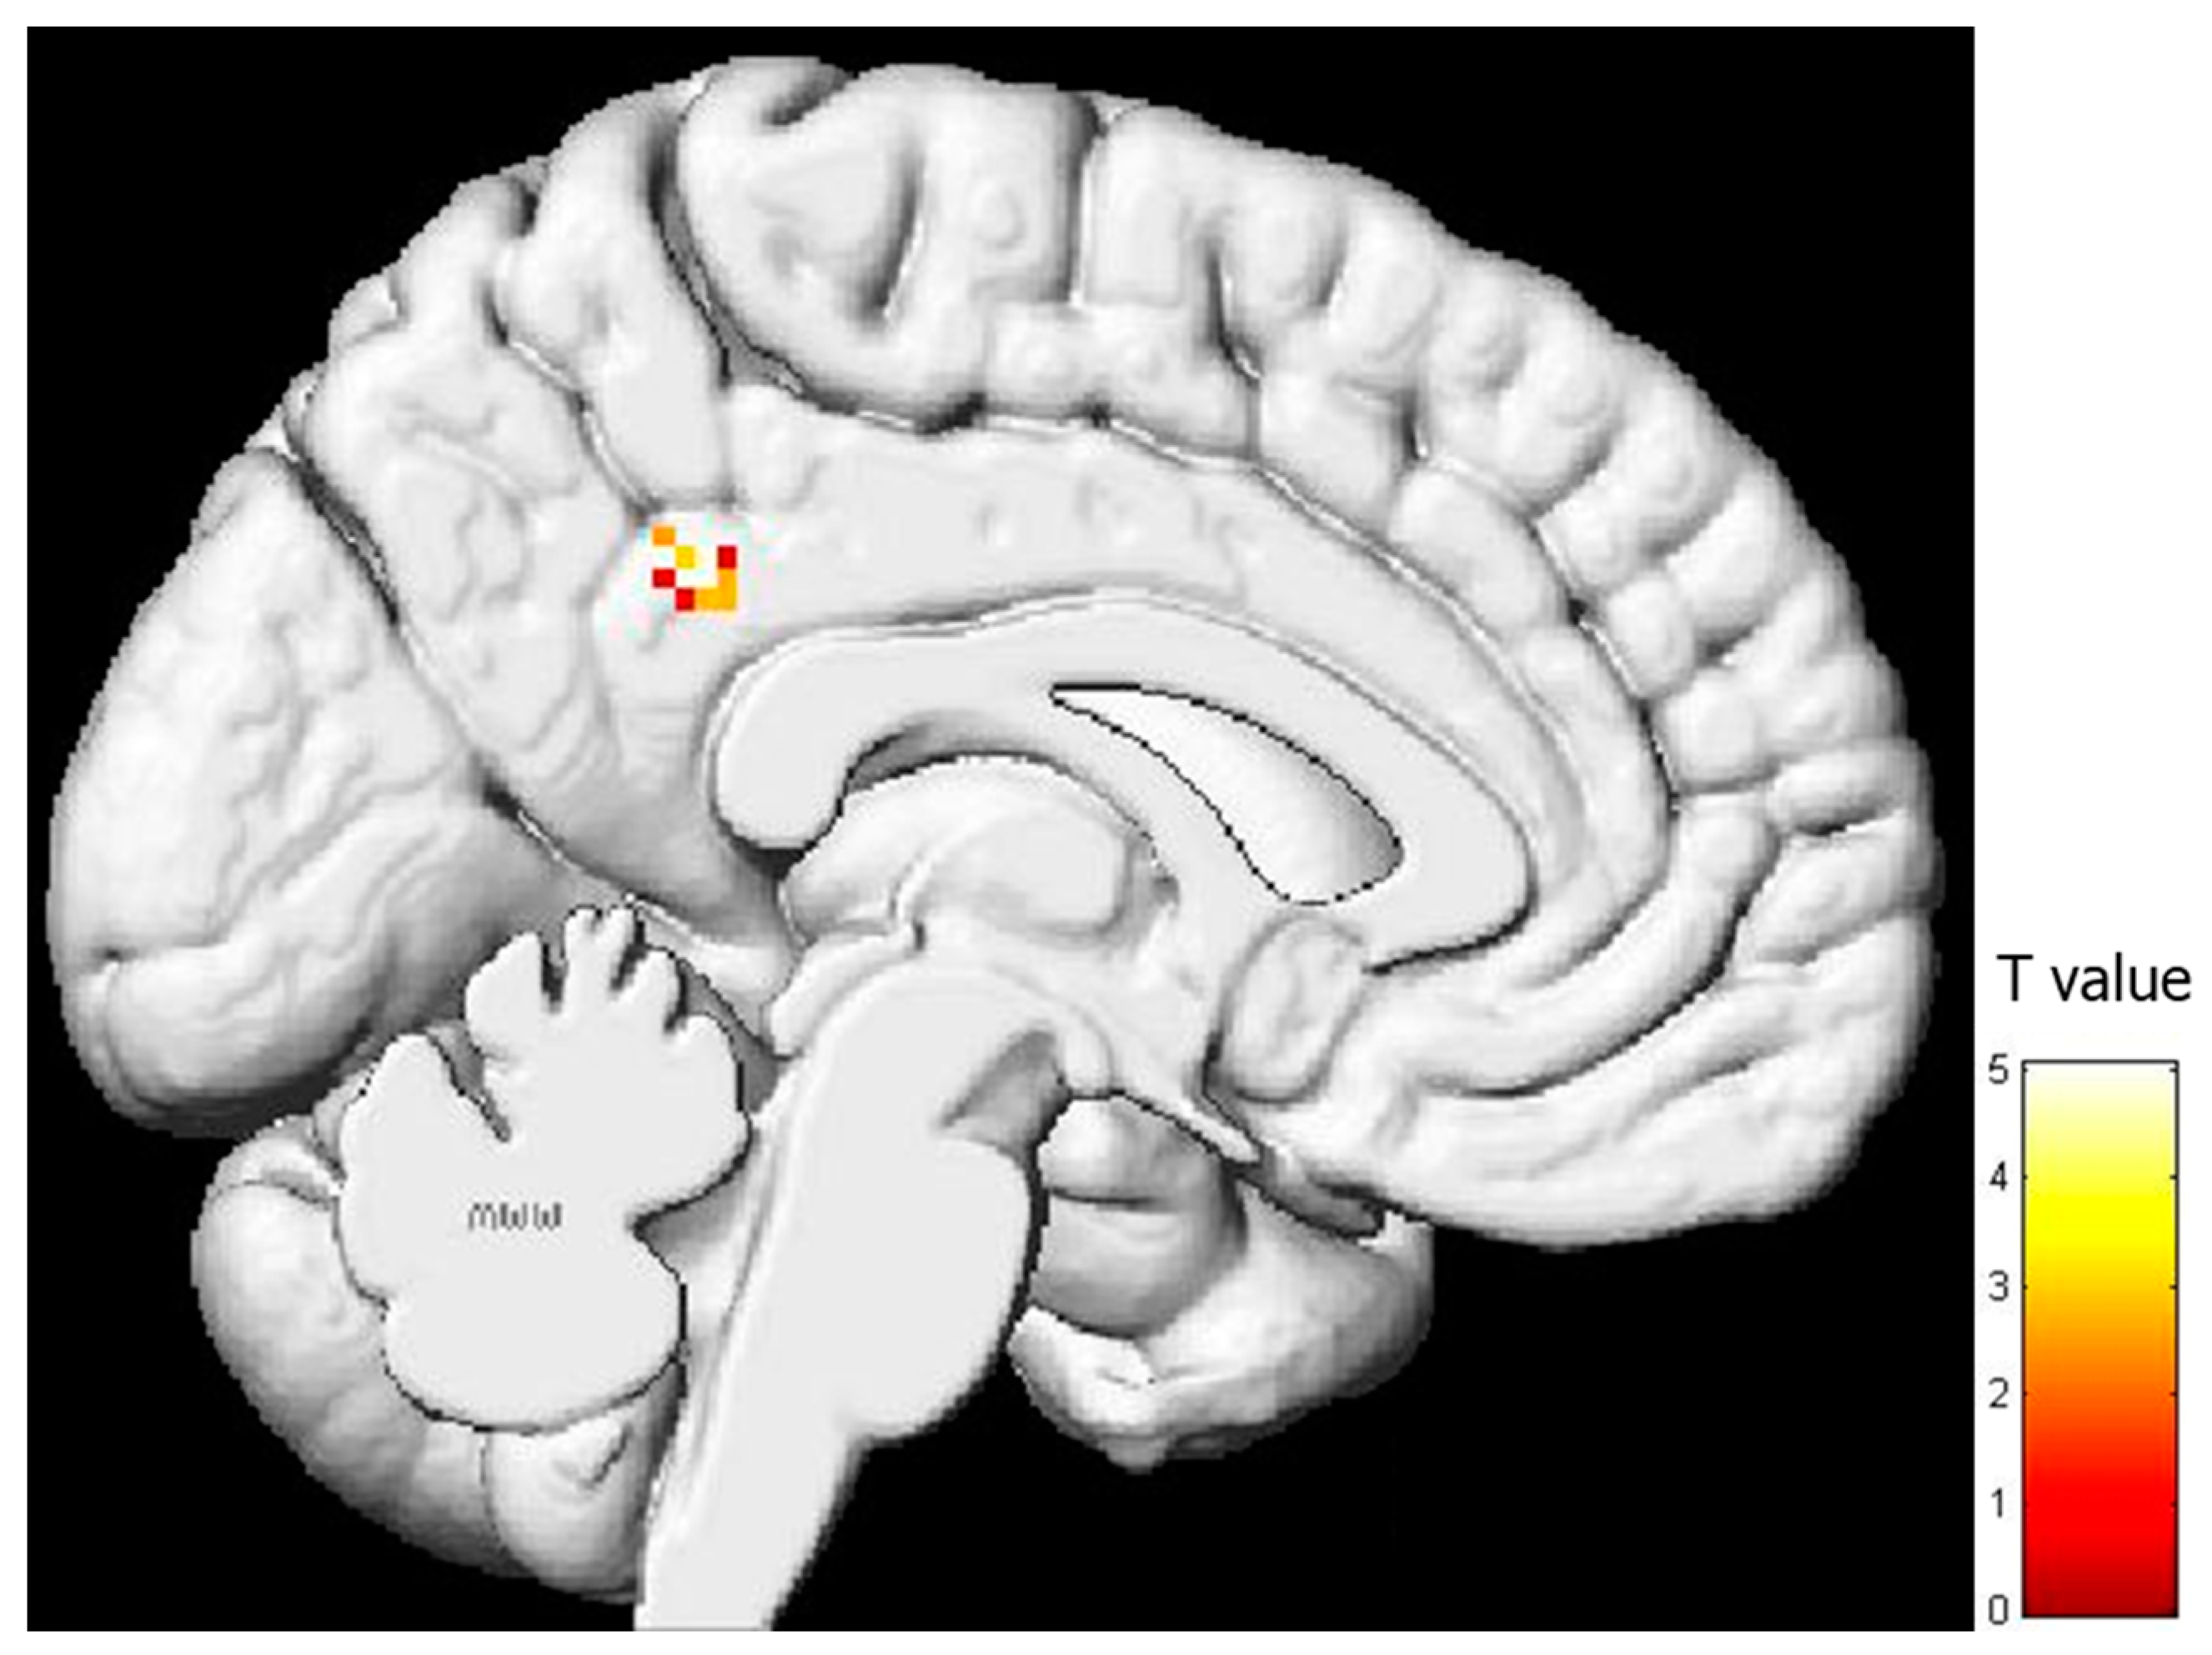

| Region | BA | x | y | z | T | Z | Voxels/Cluster | r2 |

|---|---|---|---|---|---|---|---|---|

| PARIETAL LOBE | ||||||||

| Left posterior cingulate gyrus | 31 | −14 | −44 | 32 | 5.05 | 3.39 | 25 | 0.506 |